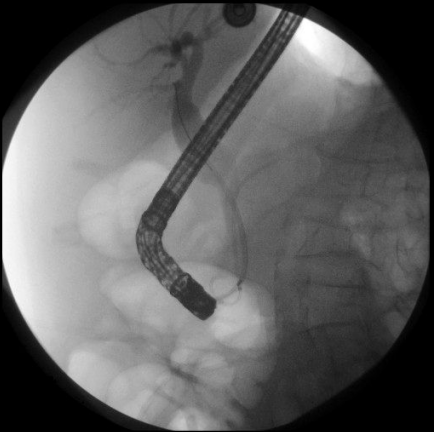

在全院会诊中,外科手术方案首先被否决。因为患者年纪大,又有基础疾病,外科手术风险极高。内镜手术虽然创伤小,但是视野比外科手术更小,操作难度很大,风险也不低。经过评估,消化内科确定行经内镜逆行性胰胆管造影(ERCP)取石,并放入支架引流。

ERCP留置胆管和胰管支架

据介绍,ERCP是一种操作难度非常高的内镜技术,十分考验医生的医术,也是诊治胆胰系统疾病的重要手段。消化内科张迎春教授拥有8000多例的ERCP经验,技巧娴熟的他将镜子一步步深入到十二指肠,通过纤细的导丝插入胰管,注入造影剂,利用取石网篮取出结石,清理胆道,沿着导丝在胰管、胆道放入支架。看到胰液流出通畅,泥沙样的胆汁排出,他长吁一口气,手术总算顺利结束。